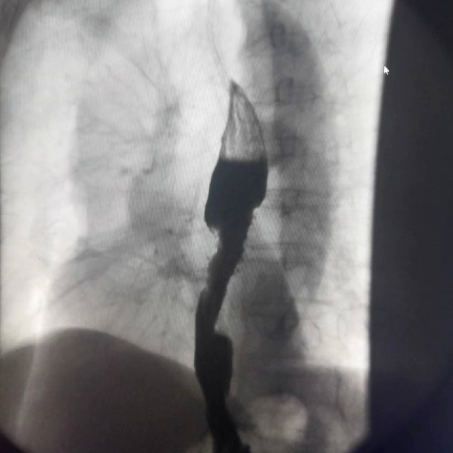

上消化道造影

數(shù)字化胃腸機可以清晰診斷食道氣管糜爛、食道靜脈曲張、食道癌、會厭綜合征、胃癌、胃竇病變、十二指腸潰瘍等病變。